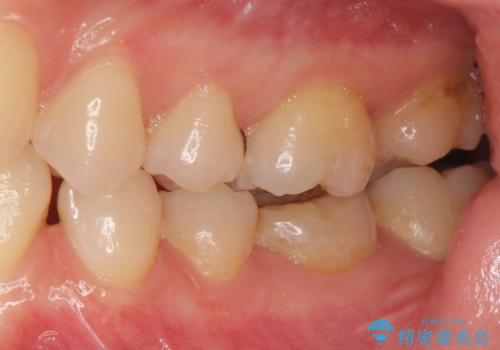

被せ物が入りました。

根管治療が終わった歯は被せ物を装着しないと細菌が根管内に侵入し根の再発のリスクが増えるため早急に被せ物を入れる事をお勧めします。